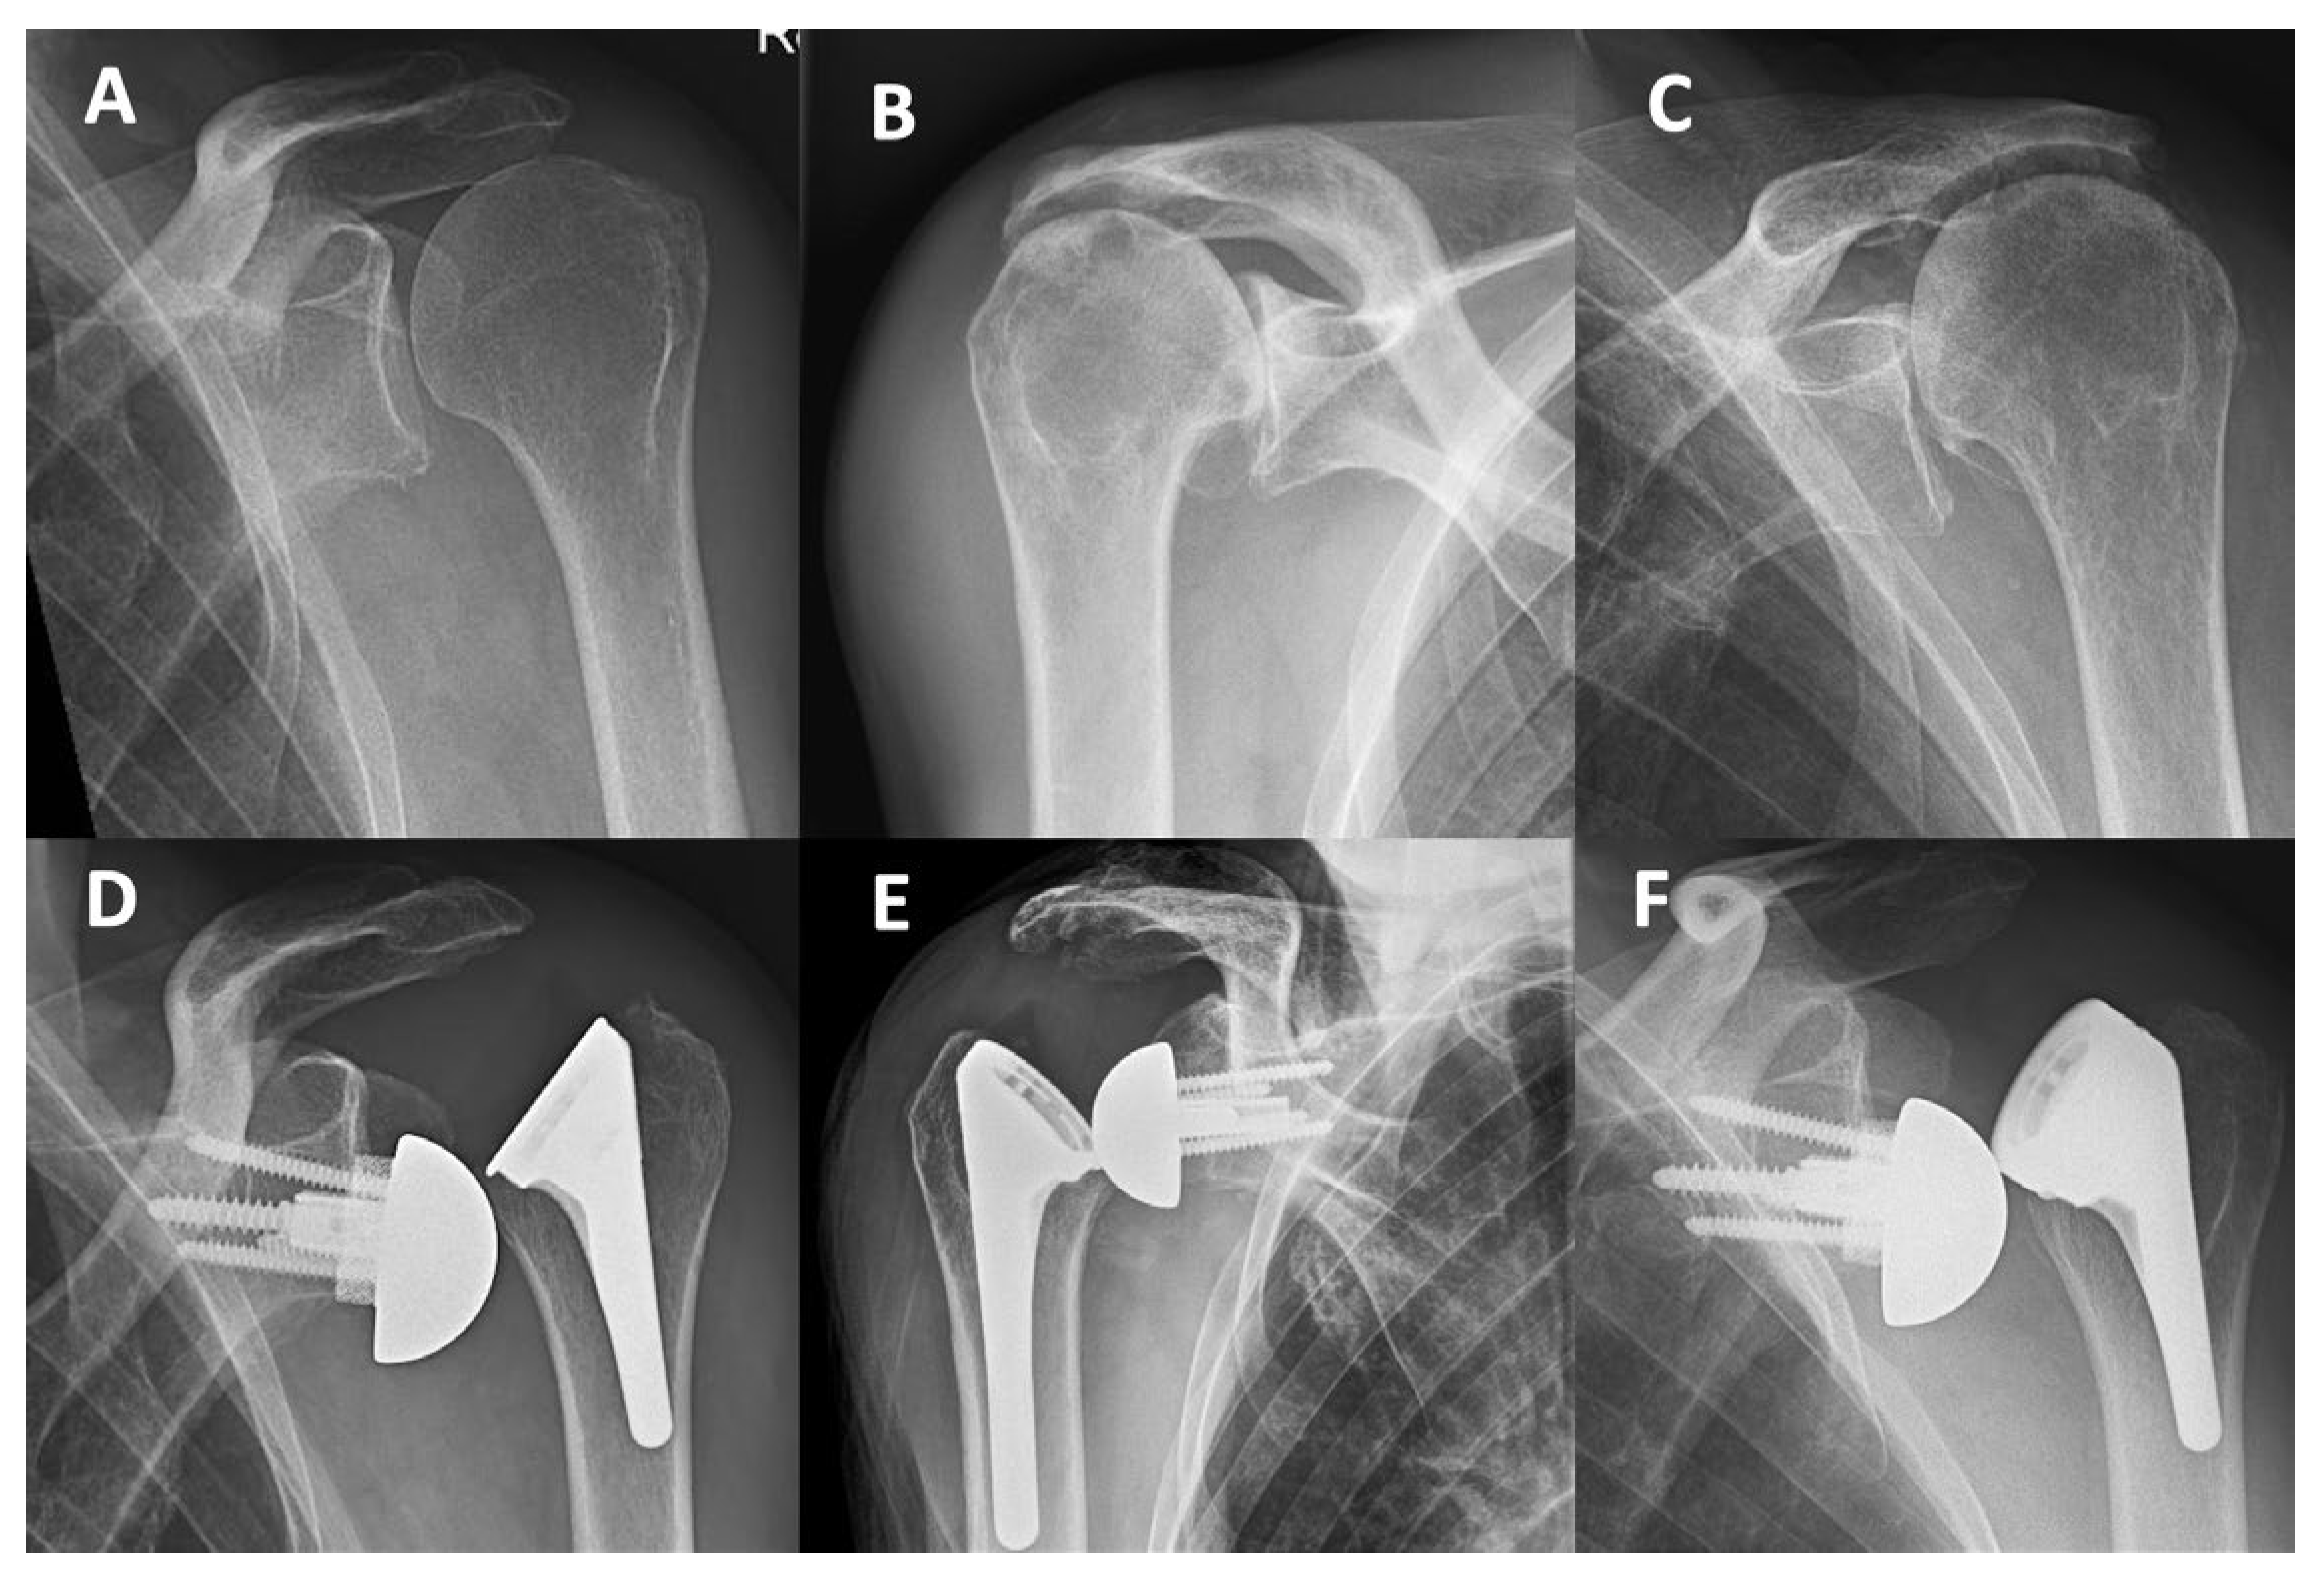

Background: In reverse shoulder arthroplasty (RSA), the neck-shaft angle (NSA) has trended downward from 155° to 135° to reduce scapular notching, but concerns about instability persist. To assess superior-lateral stability, we developed the intra-operative 2-hand-lever-test (2HLT). This study evaluates the 2HLT's effectiveness, the learning curve with a new implant, and compares liner characteristics of 155° and 135° systems. Methods: In a single-surgeon learning curve study, 81 RSA procedures with the new Perform stem (Stryker) were included. Outcomes included the 2HLT test applied in 65 cases, early dislocations, stem alignment, stem length, liner type/thickness, and complications. The early dislocation rate was compared to 167 prior Ascend Flex RSA procedures (Stryker). Liner characteristics of three 135° systems (Perform/Stryker; Univers/Arthrex; Altivate/Enovis) were compared to traditional 155° Grammont systems (Delta Xtend/DePuy; Affinis Metal/Mathys; SMR 150/Lima, Aequalis Reversed/Stryker), focusing on jump height (JH) and liner stability ratio (LSR). Results: In 75% (49/65) of cases, the 2HLT detected superior-lateral instability, influencing implant selection. The early dislocation rate in the Perform cohort was 4.9% (0% with retentive liners, 8% with standard liners) versus 0% in the Ascend Flex cohort. The mean effective NSA was 133° (127°-144°) for short Perform stems and 135° (129°-143°) for long stems. Long Perform stems significantly reduced varus outlier density below 132° and 130° (p=0.006, p=0.002). The 36mm Perform 135° standard liner has a JH of 8.1mm and LSR of 152%, markedly lower than the Altivate (10.0mm/202%) and Univers (9.7mm/193%) and similar to traditional 155° Grammont liners (8.1-8.9mm/ 147%-152%). Perform retentive liners have LSR values of 185%-219%, comparable to established 135° design standard liners (195%-202%). In the Perform cohort, early complications included 4 superior-lateral dislocations (all standard liners, LSR 147%-152%) requiring 4 revisions. Conclusions: The 2HLT effectively identified superior-lateral instability and guided implant selection. Perform standard liners have a lower LSR and JH than established 135° designs, contributing to superior-lateral instability, particularly with an effective NSA < 135°. Retentive Perform liners with an LSR > 184% have a similar LSR compared to standard liners of established 135° designs and effectively mitigated instability. We recommend discontinuing the use of non-retentive Perform RSA liners (LSR <158%).

3.1. Early Superior-Lateral Instability and Complications